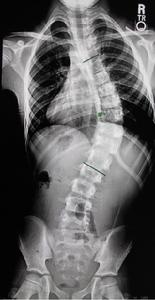

脊柱畸形根據位置可以分為頸椎,胸椎和腰椎畸形。根據形態學可以分為前凸,側凸和後凸畸形。根據脊柱畸形的原因考慮,可以分為特發性,先天性,神經肌肉型,間質性,創傷性等原因。對於側凸來說,特發性是其常見原因冠狀位畸形,將其畸形位置分為上胸段,中胸段,胸腰段/腰段。(圖1-1)

影像學方面對於脊柱側凸或者後凸的診斷標準,包括Cobb角的測量,即選擇組成側凸或者後凸兩端(最頭端和最尾端)最傾斜的椎體之間成角,是對於任何脊柱畸形最基本的描述。(圖1-2)